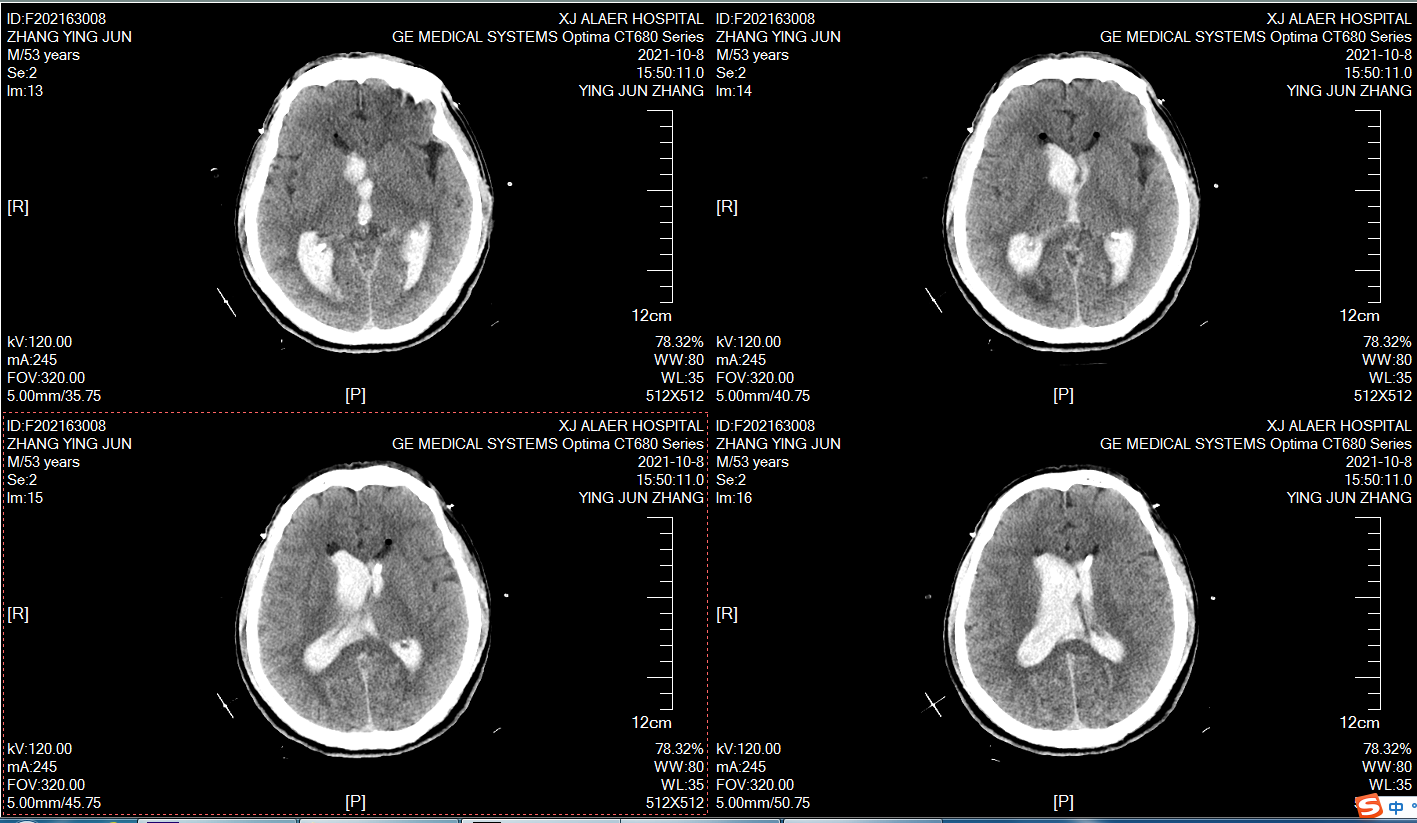

术前颅脑CT,男性,59岁,突发意识不清2小时,目前昏迷,GCS6分,右侧瞳孔4mm,左侧瞳孔2mm,脑室出血,烟雾病!

术前CTA提示烟雾病!